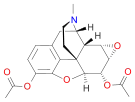

Structures

| Morphides | ||||

|---|---|---|---|---|

Codeine Codeine |

Morphine Morphine |

Oripavine Oripavine |

Pseudomorphine Pseudomorphine |

Thebaine Thebaine |